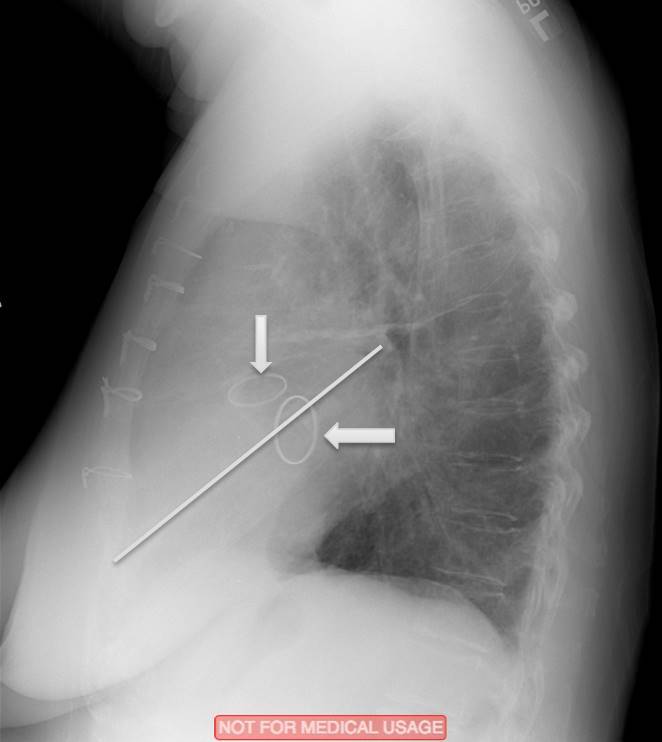

What are the indicated valves?

What valves are indicated?